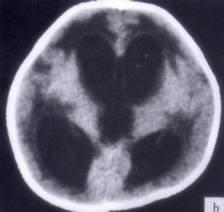

问题 病历摘要:??患者女性,10岁。结核性脑膜炎愈后8月,头痛伴恶心呕吐1周,并渐加重。体检:神清,精神差,反应迟钝,双眼底视神经乳头水肿,双眼外展差,余未见明显异常。 根据病史、CT,入院诊断考虑下列哪种?

选项 A.梗阻性脑积水 B.交通性脑积水 C.外部性脑积水 D.先天性脑积水 E.耳源性脑积水 F.良性颅内压增高 G.假性脑瘤

答案 B